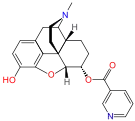

- 6-Nicotinoyldihydromorphine (metabolite of nicodicodeine)

6-nicotinoyldihydromorphine 6-nicotinoyldihydromorphine |